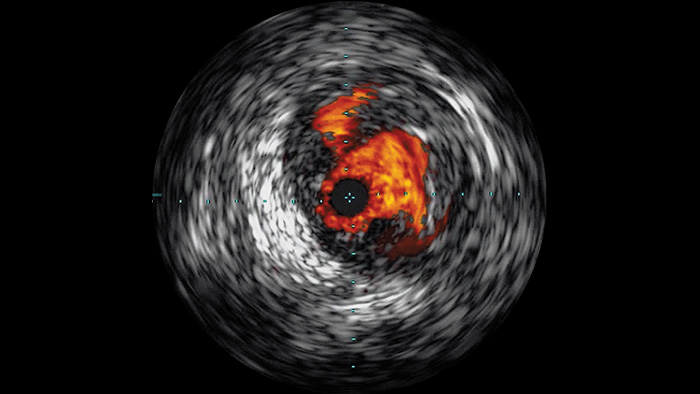

Der intravaskuläre Ultraschall (IVUS) ist eine katheterbasierte Bildgebungstechnologie, mit der Blutgefässe von innen nach aussen dargestellt werden können, um das Vorliegen und das Ausmass der Erkrankung zu beurteilen. IVUS unterstützt die Entscheidungsfindung, die Führung und die Bestätigung der richtigen interventionellen Behandlung für jeden einzelnen Patienten.

Hochauflösende Bilder von Gefässen mit hervorragender Detailgenauigkeit zur Unterstützung durchdachter Behandlungsstrategien, präziser Navigation und Verlaufsbeobachtung